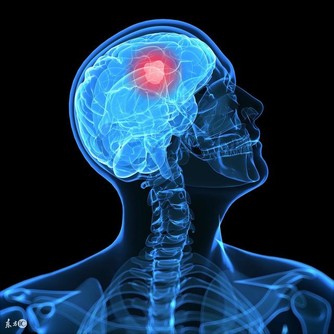

經常吃的4類藥物,正在損傷你的陽氣!

然而,在日常生活中,人們不經意間的一些行為習慣,或者經常吃的一些藥物,都可能正在損傷人體陽氣,帶大家了解一下。